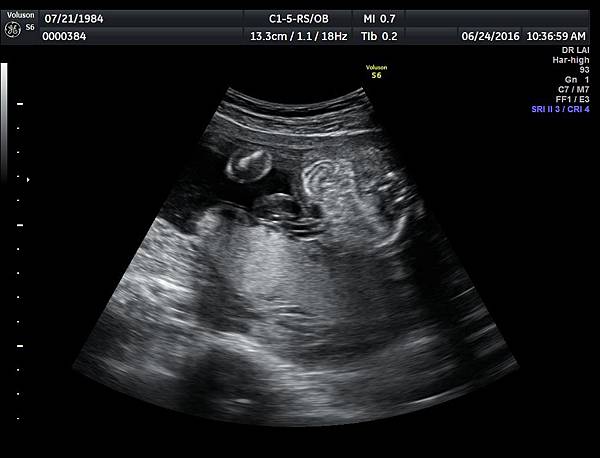

6月24日在我的診所,我幫一位懷孕22週31歲的孕婦看高層次超音波,發現胎兒的腸子很白,形狀也特別的怪( 附圖 1~12 ),我建議她做進一步相關的檢查,包括抽羊水檢查等等。